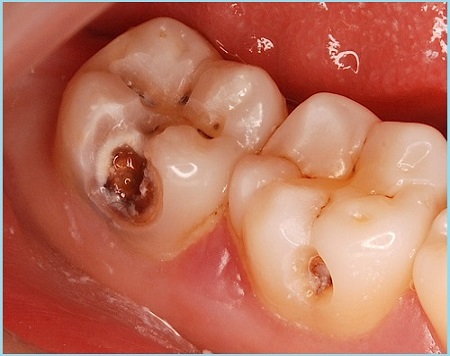

4. Глубокий. Развивается, когда в результате отсутствия лечения патологический процесс проникает в околопульпарный дентин. Кариозная полость наполнена размягченным дентином, она становиться больше, прикосновение к ней вызывает ощутимую боль. Продолжающееся деградация дентина приводит к поражению пульпы зуба, вследствие чего возникает пульпит, а в скором будущем и периодонтит.